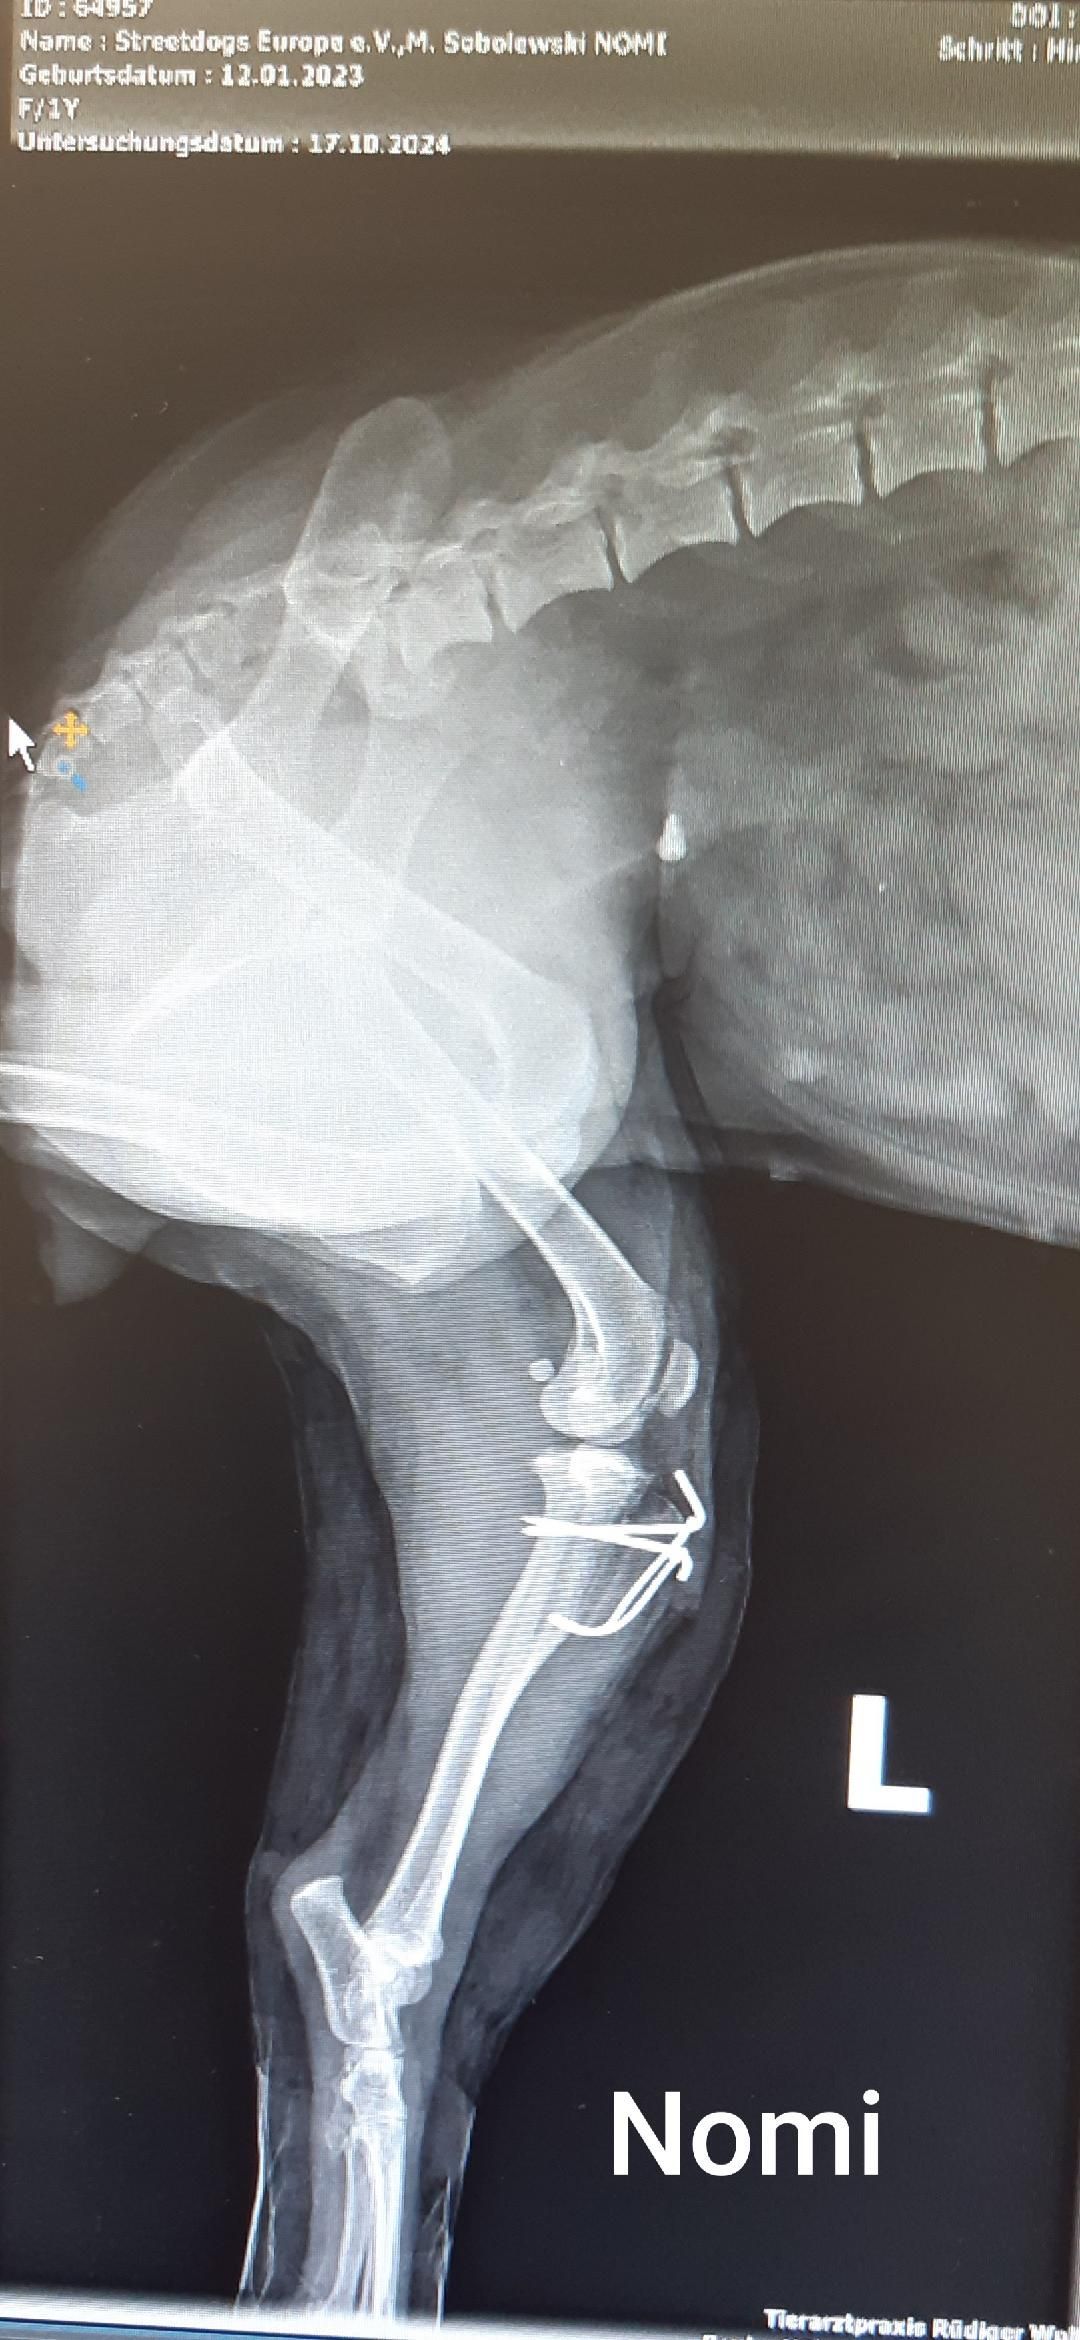

Hier seht ihr jetzt auch meine Innenfotos - da erkenne ich mich überhaupt nicht. Ich verstehe auch nicht, warum es so interessant ist, sich meine Knochen anzugucken. Aber für euch Menschen scheinen die sehr interessant zu sein.

Gestern sind wir zum Doc gefahren und da hab ich eine Spritze bekommen, nach der ich sofort eingeschlafen bin. Als ich wach wurde, war alles anders.

Ich lag in einem Käfig, hatte eine dicke Halskrause um und mein Hinterbein schmerzte wie verrückt. Mein Kopf war nicht klar und ich dachte, ich bin in der Hölle angekommen.

Mein Hinterbein ist dick eingepackt und tut verdammt weh. Ich kann es auch nicht abknicken und daher muss ich erst schauen, wie ich überhaupt Pippi machen kann.

Vorhin hat mein Pflegefrauchen mit meiner neuen Besitzerin, Annette, telefoniert. Da hab ich mitbekommen, dass mein Knie operiert wurde. Da hat der Doc irgendwas passend gefräst, einen Knochen gekürzt und die Kniescheibe in der richtigen Position befestigt. Morgen ist Kontrolle und da gibt es dann auch die Röntgenbilder.